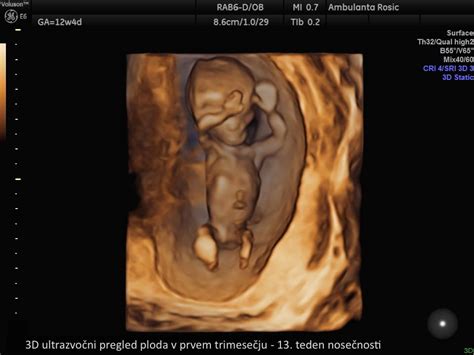

- 11. in 12. teden: Glava zavzema polovico velikosti ploda. Razvijejo se očesne veke in zametki zob, oblikujejo se jetra in zunanje genitalije, nastanejo nohti. Plod meri 4-5 cm. Od 11. tedna dalje je mogoče merjenje nuhalne svetline in biopsija horionskih resic. Nastanek organov je v 12. tednu v veliki meri zaključen, prebavila so v trebušni votlini, posteljica pa že oskrbuje plod s hrano in kisikom.

- 13. in 14. teden: Na prstih se začnejo razvijati prstni odtisi, razvite so zasnove za 20 mlečnih zob. Trebušna slinavka prične izločati inzulin. Na ultrazvoku je mogoče določiti spol. Plod v 13. tednu meri okoli 7 cm in tehta okoli 20 gramov. Opazni so dihalni gibi, plod požira plodovnico in izloča urin. Koža je poraščena z mehkimi lanugo dlačicami.